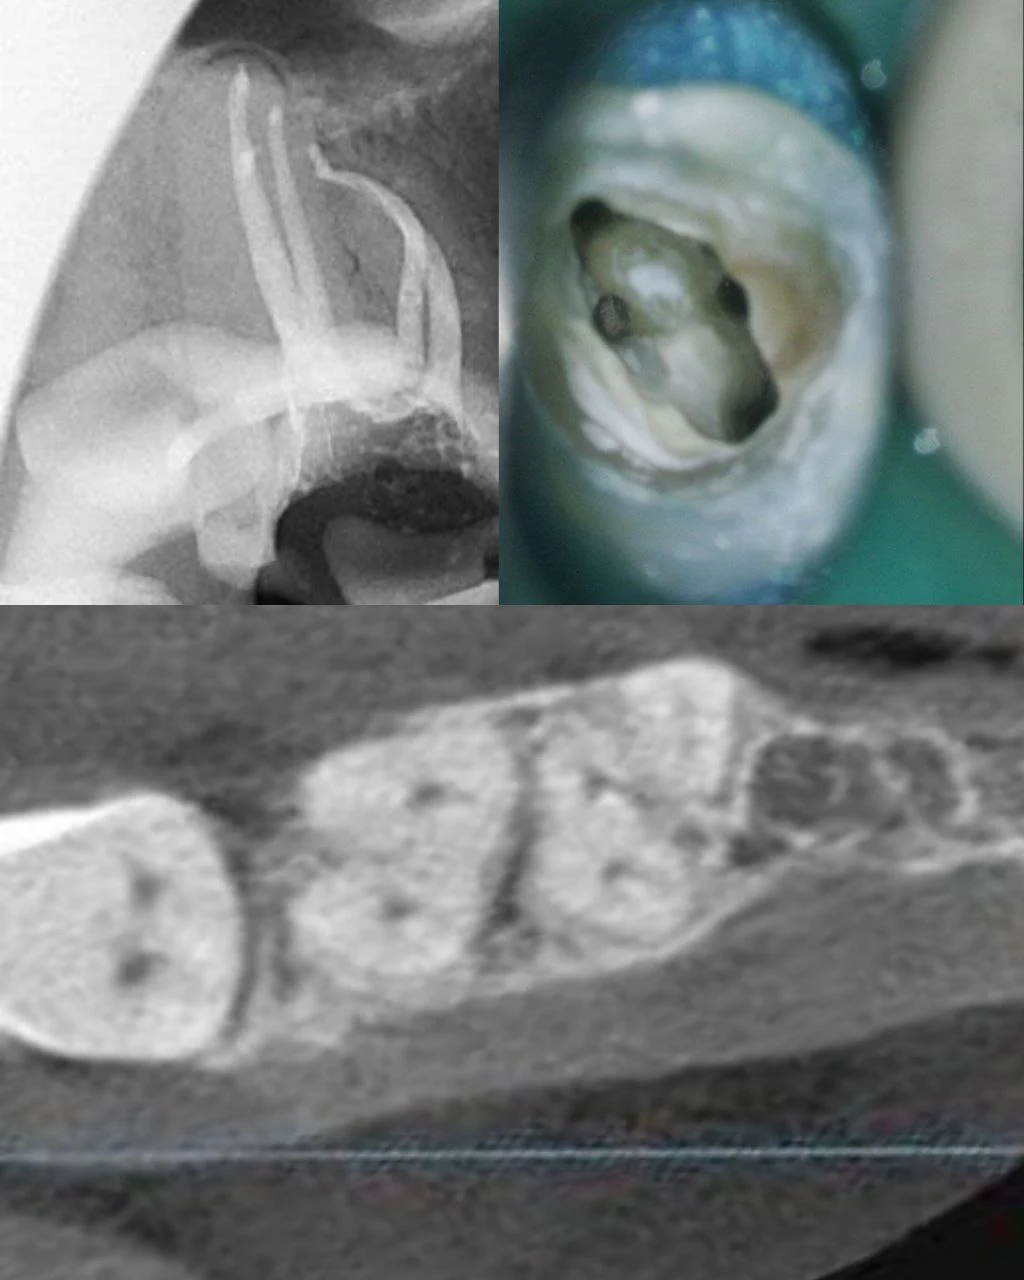

3. КЛИНИЧЕСКИЙ ПРИМЕР:

Случай: Верхний 7-й моляр, каналы расположены в одном перешейке по типу С-шейпа, не могу найти дистально-щечный канал. Работаю ультразвуком 30 минут результата ноль.

Что я сделала:

- Закрыла тефлоном зуб вместо временной пломбы

- Сделала пациенту КТ (в соседнем кабинете)

- Открыла аксиальный срез КЛКТ

- Увидела, что устье ДЩ канала находится на одной линии с устьем МВ2 канала

- Сделала фото среза на телефон

- Держала фото перед глазами во время работы

- У-файлом обработала перешеек в области предполагаемого устья ДЩ канала и углубилась на 1-2 мм

- Нашла устье ДЩ канала и зацепилась в него эндодонтическим зондом

Время: 3 минуты вместо 40.